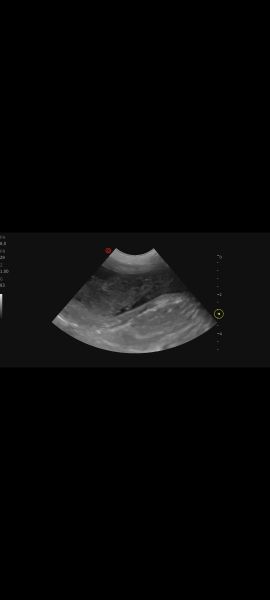

Hi, my vet performed an ultrasound on 7 year old lab mix because of an UTI .She said her bladder walls look thickened and spongy. She's concerned. Can you tell anything? I'll try to add more pics under commentsScreenshot_20251230_161511_PhotosScreenshot_20251230_161500_PhotosScreenshot_20251230_161447_Photos

Screenshot_20251230_161436_PhotosScreenshot_20251230_161425_PhotosScreenshot_20251230_161413_Photos

Hello and thankyou for sharing these pictures.  Unfortunately we do not read ultrasound scans and cannot give out emergency advice or second opinions on this site; that is your vets responsibility. What clinical signs is your dog showing?